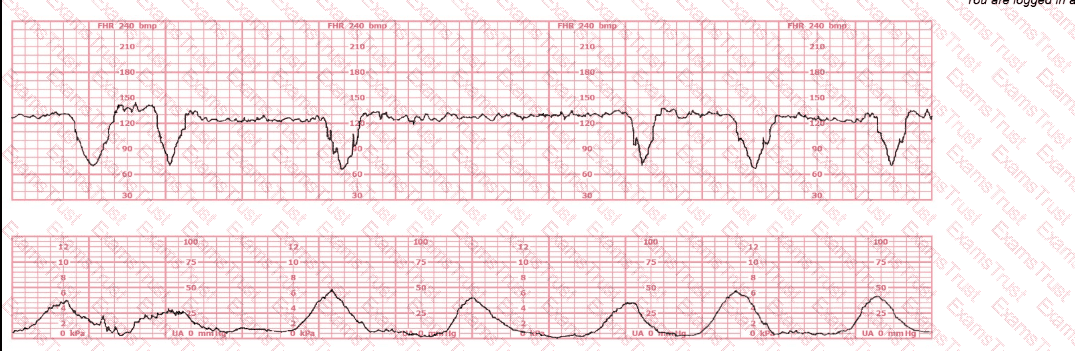

The decelerations seen in the fetal monitoring tracing shown are best described as:

This tracing reflects

The fetal heart rate tracing shown represents

This tracing is consistent with:

The most probable underlying fetal physiologic cause for this tracing would be: